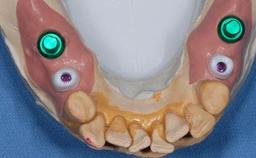

Missing Maxillary Central Incisor, Single Implant Replacement with Adjacent Tooth Restoration